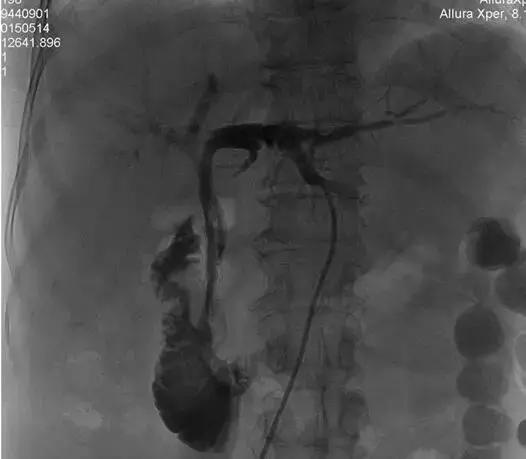

术中DSA下示意图:

1、 肿瘤病变狭窄段

2、插入射频消融导管

3、射频消融治疗及支架置入后造影再通